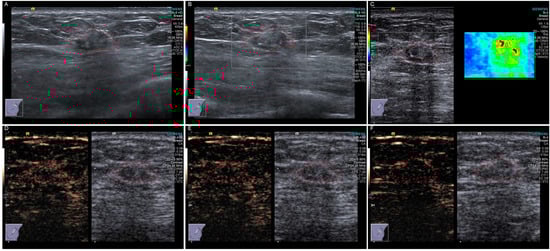

Objectives: To strengthen the recognition of juvenile xanthogranuloma (JXG) by analyzing ultrasound findings. Methods: This study retrospectively enrolled these patients with pathologically confirmed JXG from January 2011 to March 2025. The clinical, imaging, pathological features, and prognosis of all included patients were analyzed. [...] Read more.

Objectives: To strengthen the recognition of juvenile xanthogranuloma (JXG) by analyzing ultrasound findings. Methods: This study retrospectively enrolled these patients with pathologically confirmed JXG from January 2011 to March 2025. The clinical, imaging, pathological features, and prognosis of all included patients were analyzed. All the imaging features were evaluated in consensus by two radiologists. Results: Fourteen patients were included in the study. A total of 78.6% presented with solitary masses. The age of the patients ranged from 2 months to 48 years. Those aged ≤1 year accounted for 64.3% of the sample. The lesions were predominantly located on the head and face, and the skin of most patients was yellowish-orange. The ultrasound manifestations are mostly hypoechoic masses with clear boundaries and regular shapes. Contrast-enhanced ultrasound shows a slight homogeneous enhancement, and on shear wave elastography, it appears to be relatively hard. Conclusions: JXGs are more common in infants or young children and present with yellowish-orange, cutaneous lesions. Ultrasound revealed homogeneous, well-circumscribed, regular hypoechoic nodules. Multimodal imaging may be helpful for preoperative diagnosis. Full article

Figure 1